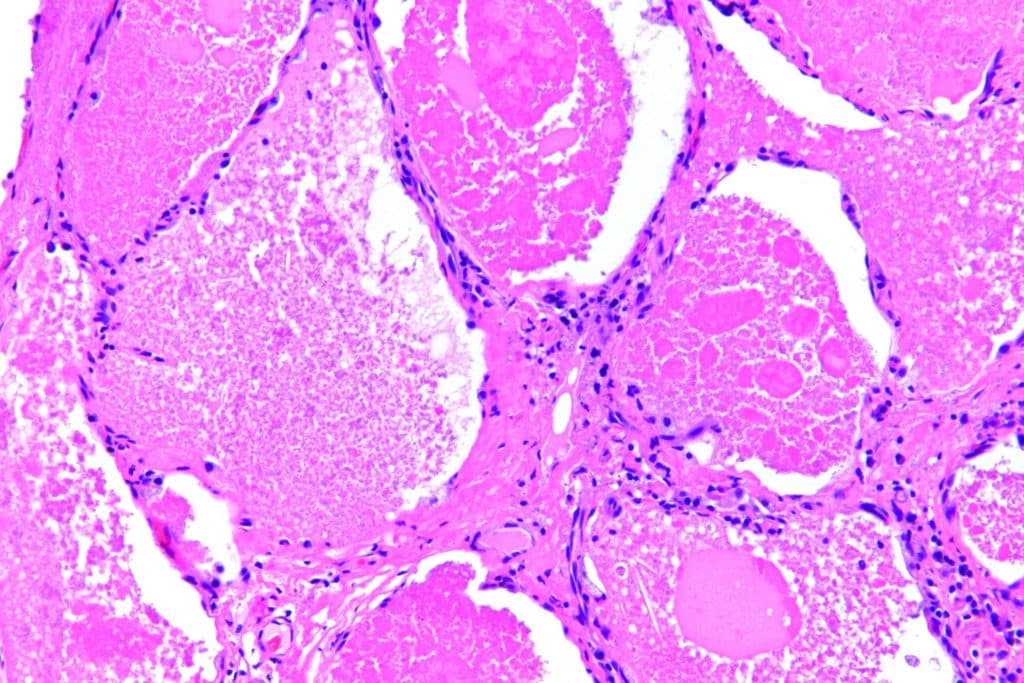

Intraalveolär findet sich ein amorphes eosinophiles feingranuläres Material mit reichlich Lipiden.